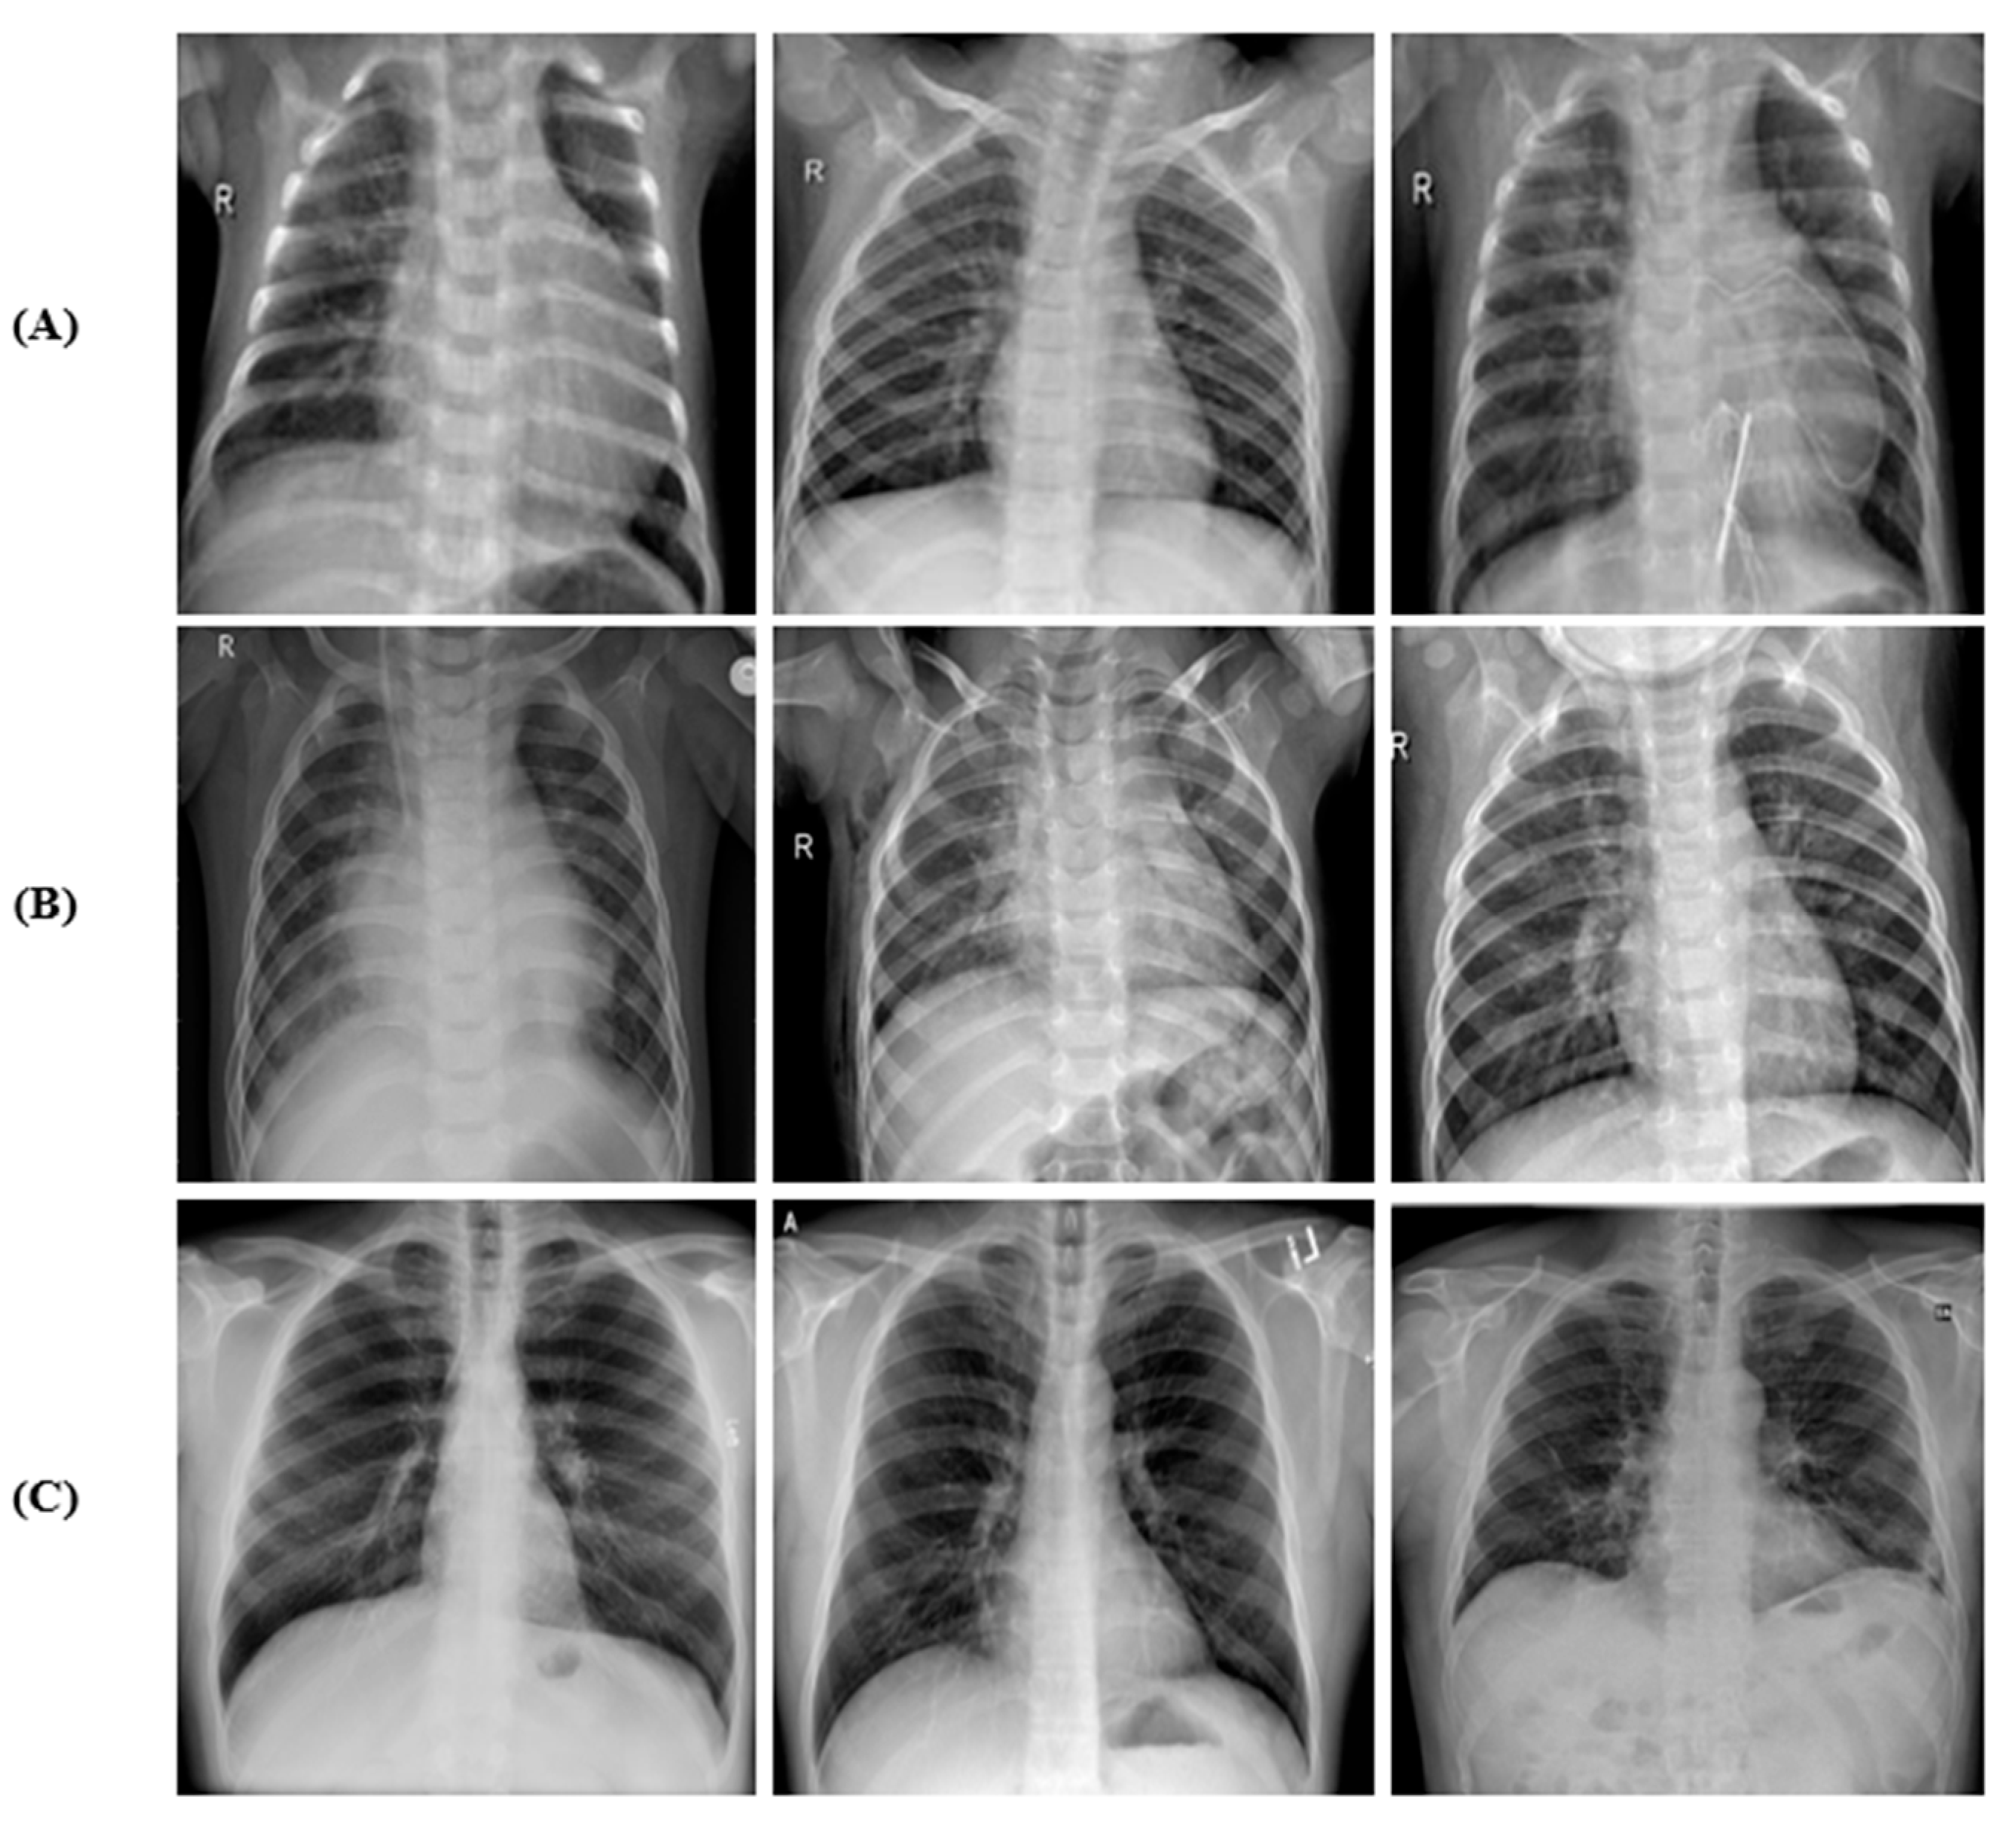

Three publicly available data repositories were used: (1) CXR images (pneumonia) dataset available on Mendeley data, which contains CXR images of healthy and non-COVID-19 pneumonia [27]; (2) augmented COVID-19 X-ray images dataset [28]; and (3) COVID-19 image data [29] for CXR images of COVID-19 pneumonia. The representative CXR images of healthy, non-COVID-19 pneumonia, and COVID-19 in the combined dataset are shown in Figure 1.

Figure 1. Sample of CXR images: (A) healthy, (B) non-COVID-19, and (C) COVID-19.